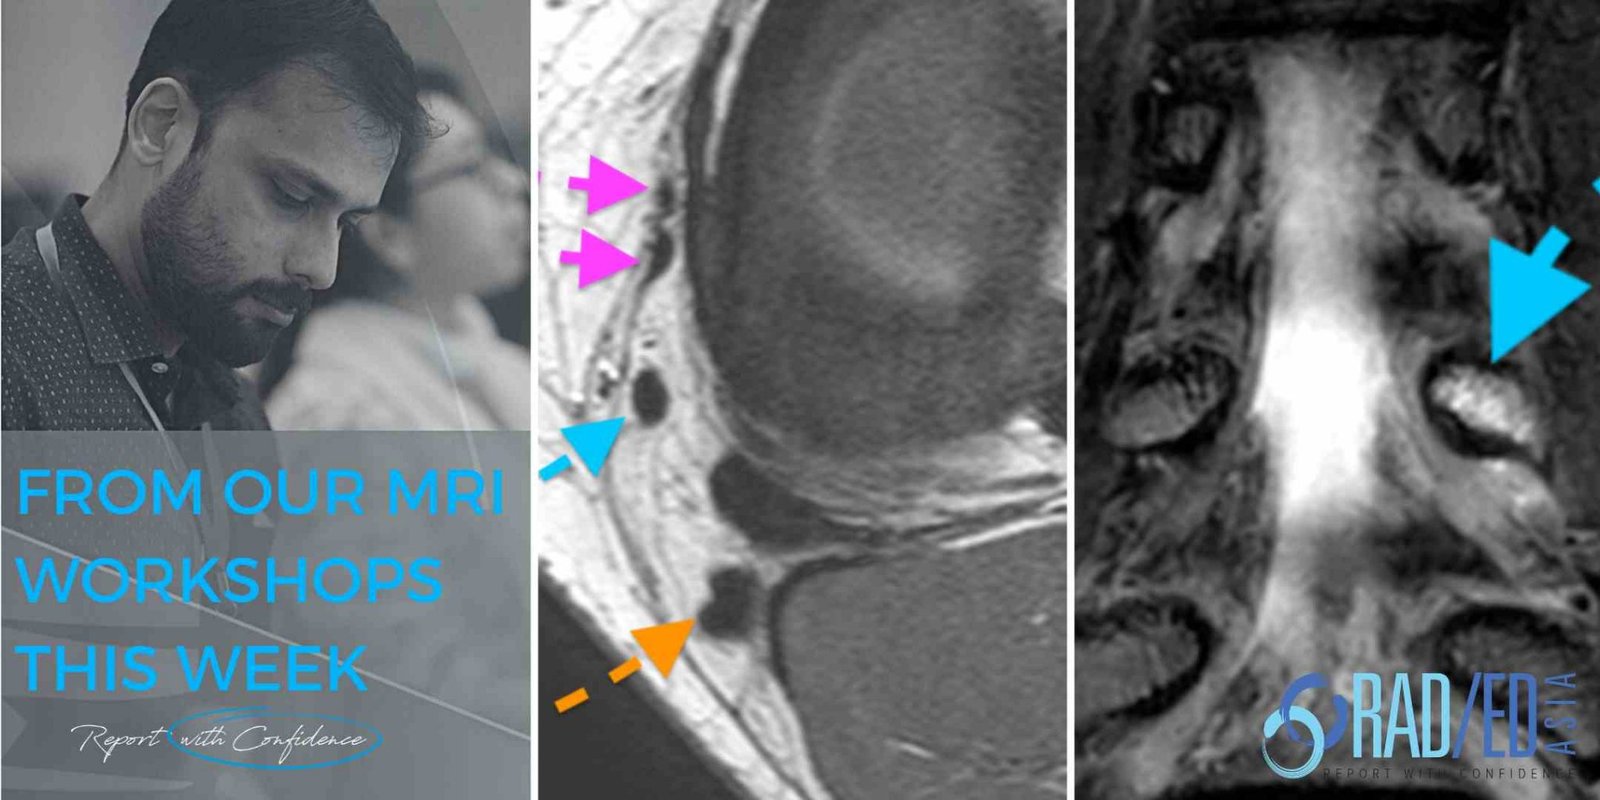

From radedasia.com

LEARN MSK MRI LEARN SPINE MRI WHATS THE Dx Radedasia Anatomy Mri Msk Mr is the best imaging modality to examen patients with shoulder pain and instability. Explore detailed mri anatomy of the ankle with educational resources available on freitasrad.net. Musculoskeletal mri atlas wait a few seconds for all the images to load and scroll using your mouse wheel Our goal is to share an introductory approach. About anatomy mri magnetic resonance imaging. Anatomy Mri Msk.

MSK MRI COURSES KEY POINTS FROM OUR MSK MRI COURSES Radedasia Anatomy Mri Msk About anatomy mri magnetic resonance imaging is particularly well suited for the medical evaluation of the musculoskeletal (msk). Musculoskeletal mri atlas wait a few seconds for all the images to load and scroll using your mouse wheel Shoulder anatomy and variants on mri; Stanford msk mri atlas has served ~1.7m pageviews to users in over 100 countries. Mr is the. Anatomy Mri Msk.